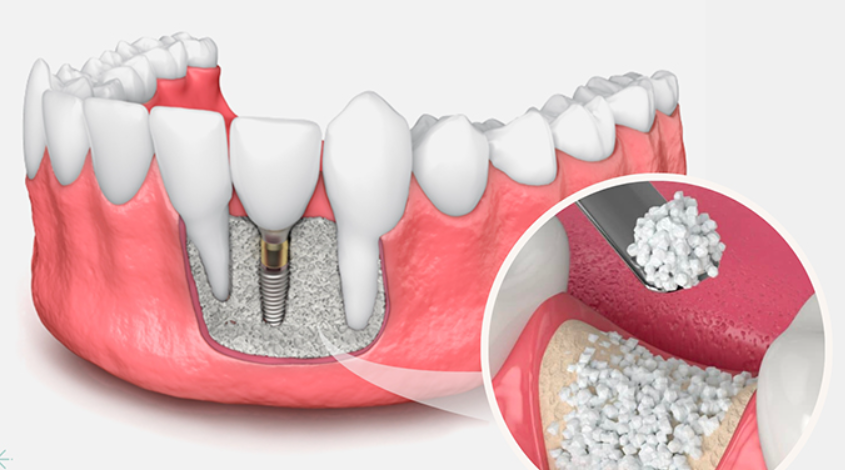

5. 이식 재료의 배치

추출 혹은 채취한 임플란트 뼈이식 재료는 원하는 위치에 배치됩니다. 어떤 경우에는 이식편을 덮기 위해 특수 막을 사용할 수 있습니다. 이 막은 연조직 및 박테리아가 뼈 이식편으로 침입하는 것을 방지하고 뼈 재생을 도와줍니다.

임플란트 뼈이식으로 뼈재생이 충분히 이루어졌음을 치과의사가 방사선 사진을 통해 확인하면 임플란트 식립을 진행할 수 있습니다.